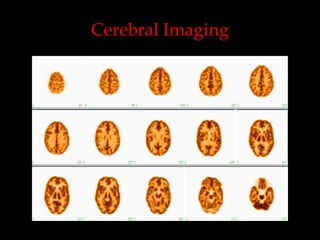

Cerebral Imaging

99mTc-HMPAO

: cross to BBB and fix in the brain

proportionally to perfusion

18FDG : glucose metabolism

99mTc-TRODAT : dopamine transporter

111In-DTPA, 99mTc-DTPA : CSF dynamics, V-P

shunt patency study